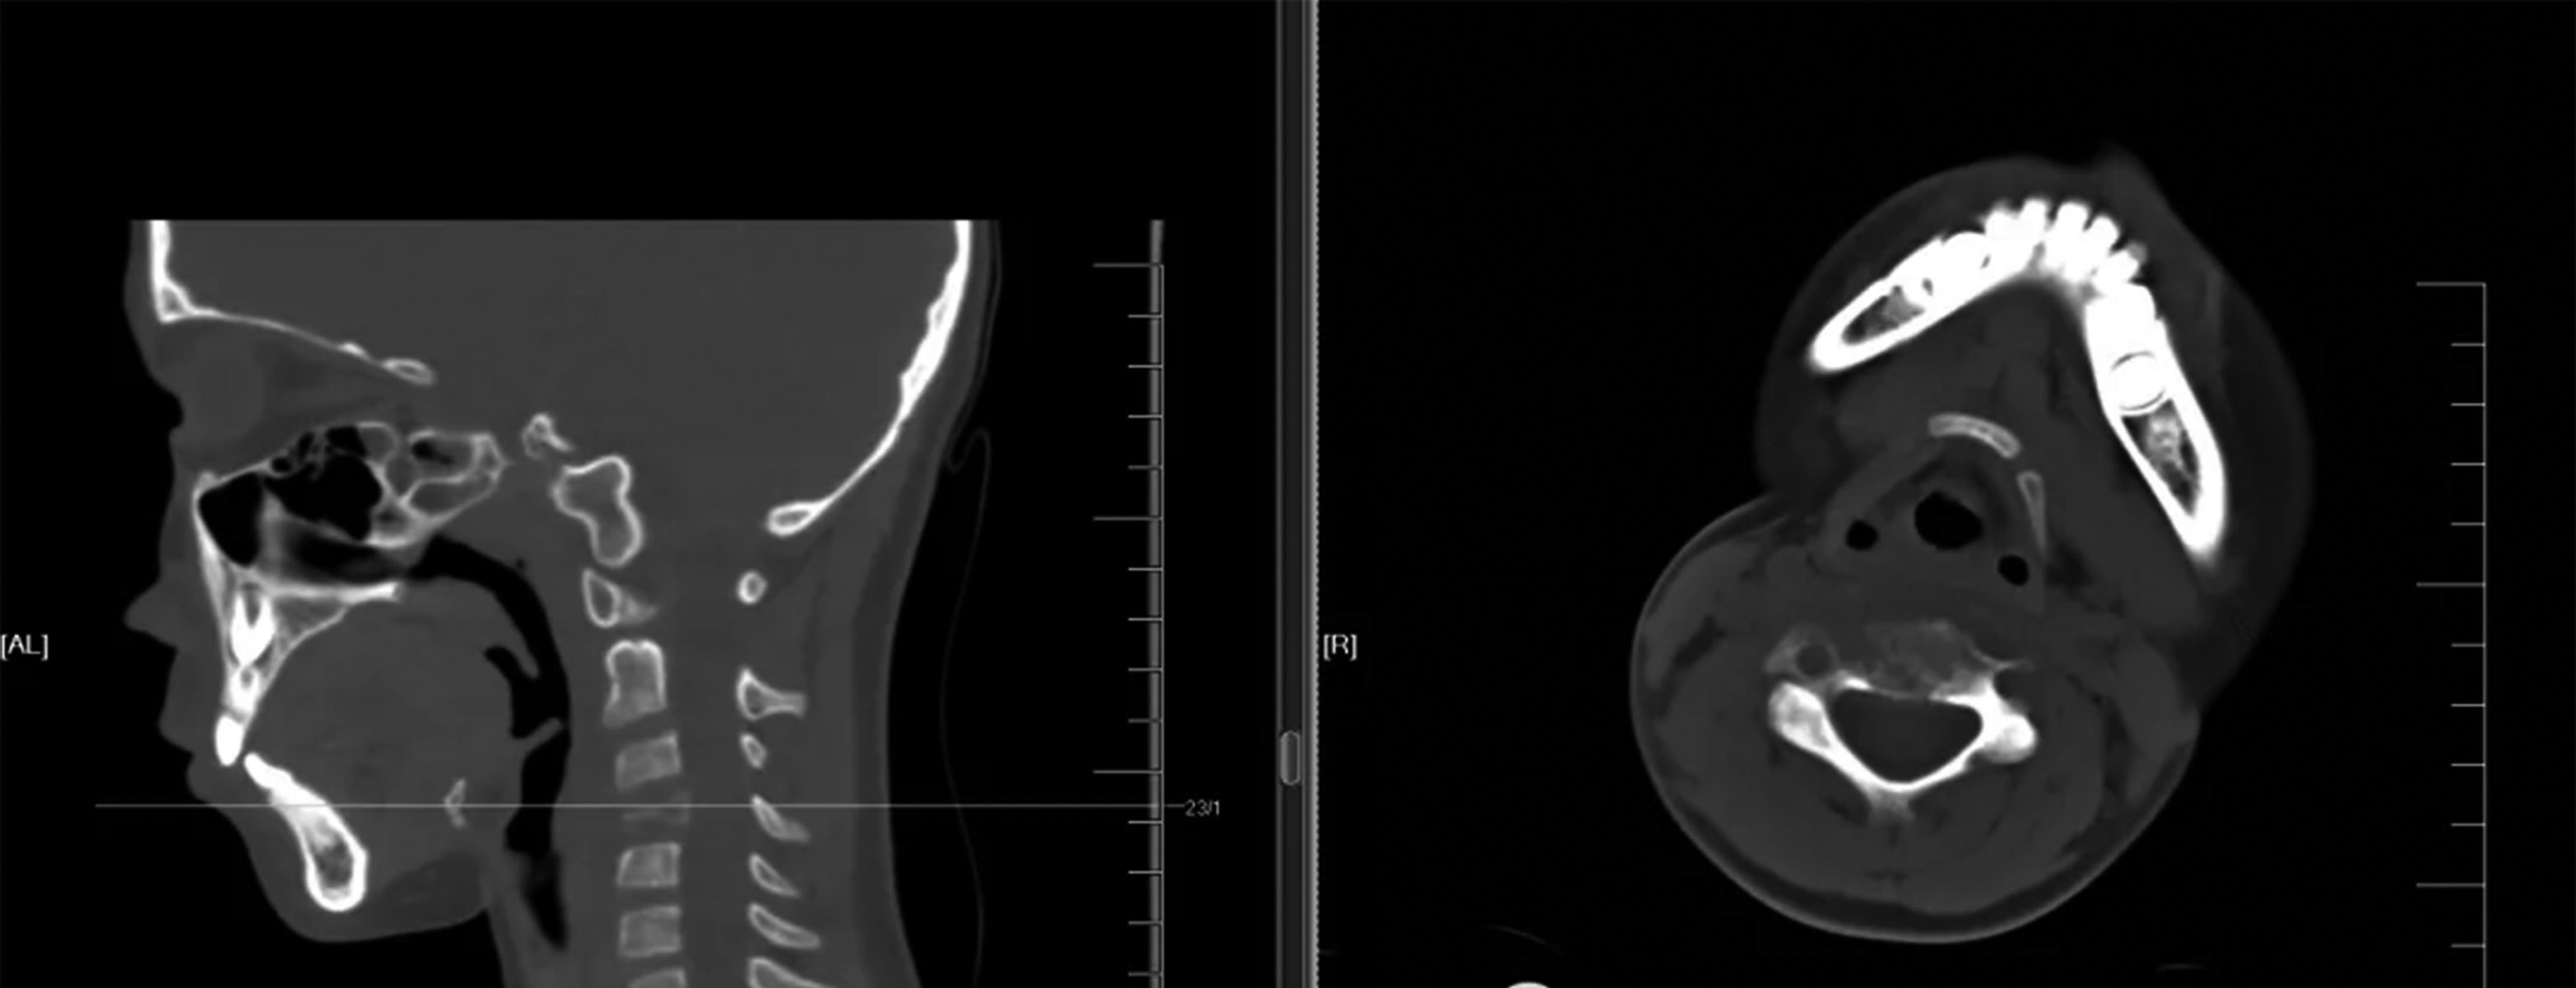

朗格汉斯细胞组织细胞增生症(LCH)是一种涉及朗格汉斯细胞克隆增殖的罕见疾病,其特征是组织细胞(被激活的树突状细胞和巨噬细胞)的异常增殖。该病与其他形式的白细胞异常增殖有关,可分为局部的骨嗜酸性肉芽肿(EG)和罕见的多系统综合征。 骨嗜酸性肉芽肿在骨肿瘤中的占比不到1%,好发于婴幼儿及青少年,尤其是10岁以下的儿童;好发部位为颅骨、下颌骨、脊柱、肋骨和长骨。其发病机制尚不清楚,可能与病毒、细菌、遗传因素及免疫功能障碍有关。实验室检查结果提示血沉加快、白细胞增多或嗜酸性粒细胞计数增多等。 四肢嗜酸性肉芽肿最常发生于股骨,然后为胫骨,之后为肱骨;病灶发生的位置多为骨干,其次是干骺端,发生于骨骺者极为少见。典型X线表现为穿孔型溶骨性病变,无反应性硬化症;存在较为成熟的骨膜反应,骨膜反应与骨皮质间可见透亮线,无放射状骨针形成;可伴有范围较广的软组织肿胀,但其边界清晰,密度和信号较均匀。 鉴别诊断:浆细胞瘤、多发性骨髓瘤、软骨炎等。 脊柱嗜酸性肉芽肿最常见的发病位置是胸椎,然后是腰椎和颈椎。临床症状取决于病变椎体的位置,常见症状有背部或颈部疼痛,进行触诊时脊柱有压痛和活动范围受限,或斜颈。病椎椎体骨质呈溶骨性破坏,进行X线检查时可以观察到椎体的密度不均伴空气影,形态呈楔形改变,椎间隙正常或增宽,典型表现为“扁平椎”。患者进行CT检查时,医生可以清楚地观察到早期椎体以溶骨性破坏为主,病灶周围可见不规则的斑点状骨性残片,晚期以骨质硬化增生为主,在缺损的骨质边缘可伴有硬化增生,出现混杂的密度改变。椎体可呈现“扁平椎”或楔形改变,椎旁可见软组织肿块影分布。MRI(磁共振)检查结果提示,早期椎体信号的异常改变以及软组织肿块的侵袭,随着病程的进展,椎体严重破坏呈“扁平椎”或“铜板椎”;软组织肿块在椎体周围分布,其信号变化基本与病椎一致,具有一定的特异性。 鉴别诊断:尤因肉瘤、骨肉瘤、淋巴瘤、转移瘤和成骨不全等。当临床症状和影像学表现不明确时,患者需要做组织活检。根据活检结果,医生进行组织学诊断。CT引导下的活检对嗜酸性肉芽肿的组织学诊断是有效的,诊断准确率为70%~100%。 骨嗜酸性肉芽肿的治疗方法包括观察和固定、吲哚美辛治疗、甲基强的松龙注射、射频消融术、局部切除和刮除伴或不伴植骨、化疗和放疗,复发率低于20%。1.无症状患者典型单发病灶可选择保守治疗;脊柱孤立嗜酸性肉芽肿伴轻度神经症状者,可进行固定和放疗,低剂量放疗可有效限制疾病进展,但是可能损害软骨内生长板,限制骨愈合和重建,或导致放射引起的继发性疾病,如放射后肉瘤和脊髓炎。2.朗格汉斯细胞悬液可产生白细胞介素(IL)和前列腺素(PG),甲基泼尼松龙可抑制IL-1诱导的骨吸收和前列腺素生成,对于小于受累骨直径一半的小病变,建议最低剂量为40毫克,对于骨盆的大病变,建议最高剂量为160毫克。3.单发嗜酸性肉芽肿不推荐化疗;化疗应到全身累及时进行,或作为儿童单发病灶无法进行安全、完整的手术切除时的初始治疗。4.若保守治疗效果不佳,出现严重的脊柱后凸畸形或神经功能损伤,应尽早采取手术治疗。手术治疗包括开放性手术和微创手术,脊柱嗜酸性肉芽肿的开放性手术指征主要为:神经症状明显,脊柱稳定性差,畸形严重,保守治疗无效且病程进展较快等。微创手术包括经皮椎体成形术和CT引导下经皮穿刺注射药物;适应证主要为疼痛症状明显,脊柱压缩但神经症状不明显,脊柱稳定性好。 病例:孙某,9岁,男,因“颈部间断疼痛伴活动受限3周,加重1周”入院。患儿3周前无明显诱因出现颈部轻微疼痛,伴轻度活动受限,四肢运动、感觉正常,未在意,未进行诊治。1周前,患儿颈部疼痛伴活动受限加重,到医院就诊。颈椎CT检查结果提示:C4椎体内骨质破坏。患儿来到河南省肿瘤医院就诊,入院后完善相关检查。根据检查结果,医生考虑C4嗜酸性肉芽肿。对患儿予以卧床、颈椎牵引、口服强的松治疗3周,其颈部疼痛明显好转。患儿进行颈椎CT复查,未见病变进展。嘱咐患儿出院后佩戴颈托,继续用药,定期复查。 (作者供职于河南省肿瘤医院)